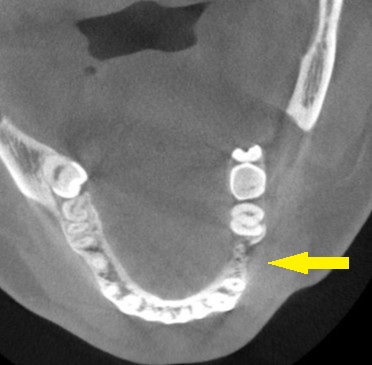

CTを撮影してみると、確かに、骨幅が狭く、十分な骨の厚みを確保してインプラントを長期に安定した状態にしたいとなると、骨を増やす手術が必要でした。

人工骨を使用しての骨造成術を併用して、インプラント埋入を行なうことで了承されましたので、本日、同手術を施行しました。

下の写真に手術前後のCTを示します。